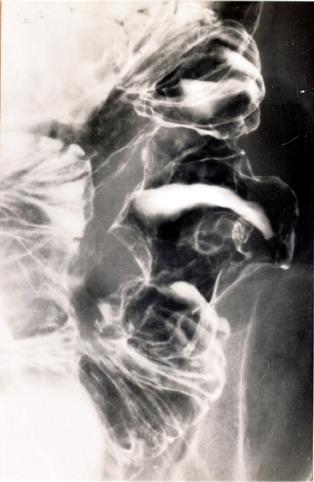

림프계종양 악성림프종 (소장)

다발성의 종양을 형성한 소장의 악성 림프종

[Image-ID:5402]

악성 림프계종양/악성 림프종

소장/공장

X-P

40이상

다발종양(동일 장기)

유(동시성)